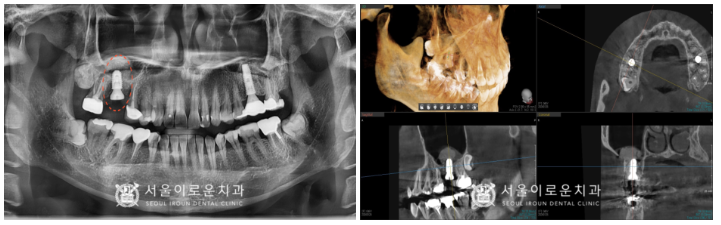

위턱 오른쪽 첫 번째 큰 어금니(#16)의

치아 뿌리 쪽으로 파절 되어있는 것을

확인할 수 있었고,

주변 잇몸뼈의 흡수가 심하고

동요도 또한 심한것을 체크할 수 있었습니다.

이 경우 살려 쓰기 어려울 것으로 판단되어

안타깝게도 발치가 필요한

상황이었습니다.

발치 후 임플란트를 고려해야 하는 상황인데,

뿌리 쪽 잇몸뼈의 흡수가 심해

남아 있는 뼈의 양도 작고,

상악동도 많이 내려와 있는 상황이었는데요.

이 경우 내려와있는 상악동을 올리고

뼈이식을 진행하는

‘상악동 거상술’을 동반한

임플란트 식립 계획을 수립하였습니다.

파노라마 뿐만 아니라

치근단 사진, 3D-CT를 통해

구강 내 해부학적 구조물과

상악동과의 거리 등을 파악하고,

임플란트의 식립 위치 및 방향 등

여러가지 사항을 고려하여

발치 후 수술을 진행하였답니다.

잔존 뼈와 상악동과의 수직적인 높이가

3mm가 채 되지 않아

상악동 거상술 중 ‘측방 접근법’을 활용하여

수술을 진행하였습니다.